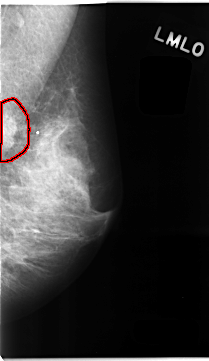

FILE: C_0107_1.LEFT_MLO.OVERLAY

TOTAL_ABNORMALITIES 1

ABNORMALITY 1

LESION_TYPE MASS SHAPE IRREGULAR MARGINS ILL_DEFINED

ASSESSMENT 5

SUBTLETY 5

PATHOLOGY MALIGNANT

TOTAL_OUTLINES 1

BOUNDARY